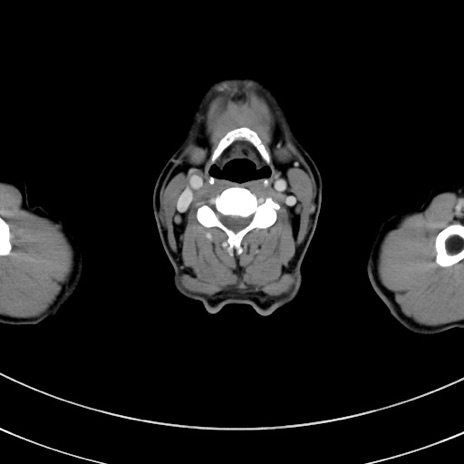

冠状断像